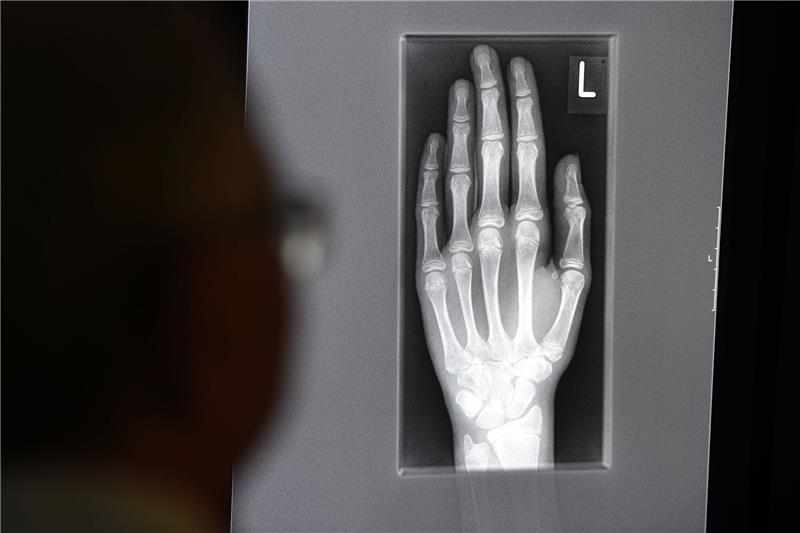

Ein Röntgenbild auf einem Bildschirm zeigt in einem Klinikum in Baden-Württemberg die linke Hand eines jungen Menschen im Alter zwischen 16 und 19 Jahren.